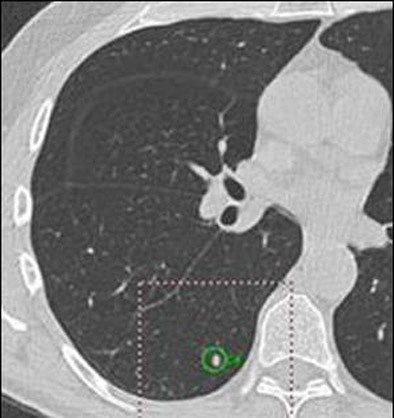

| A 5-mm nodule in right middle lobe, representing a true-positive CAD finding. All images courtesy of Dr. Heidi Roberts. |